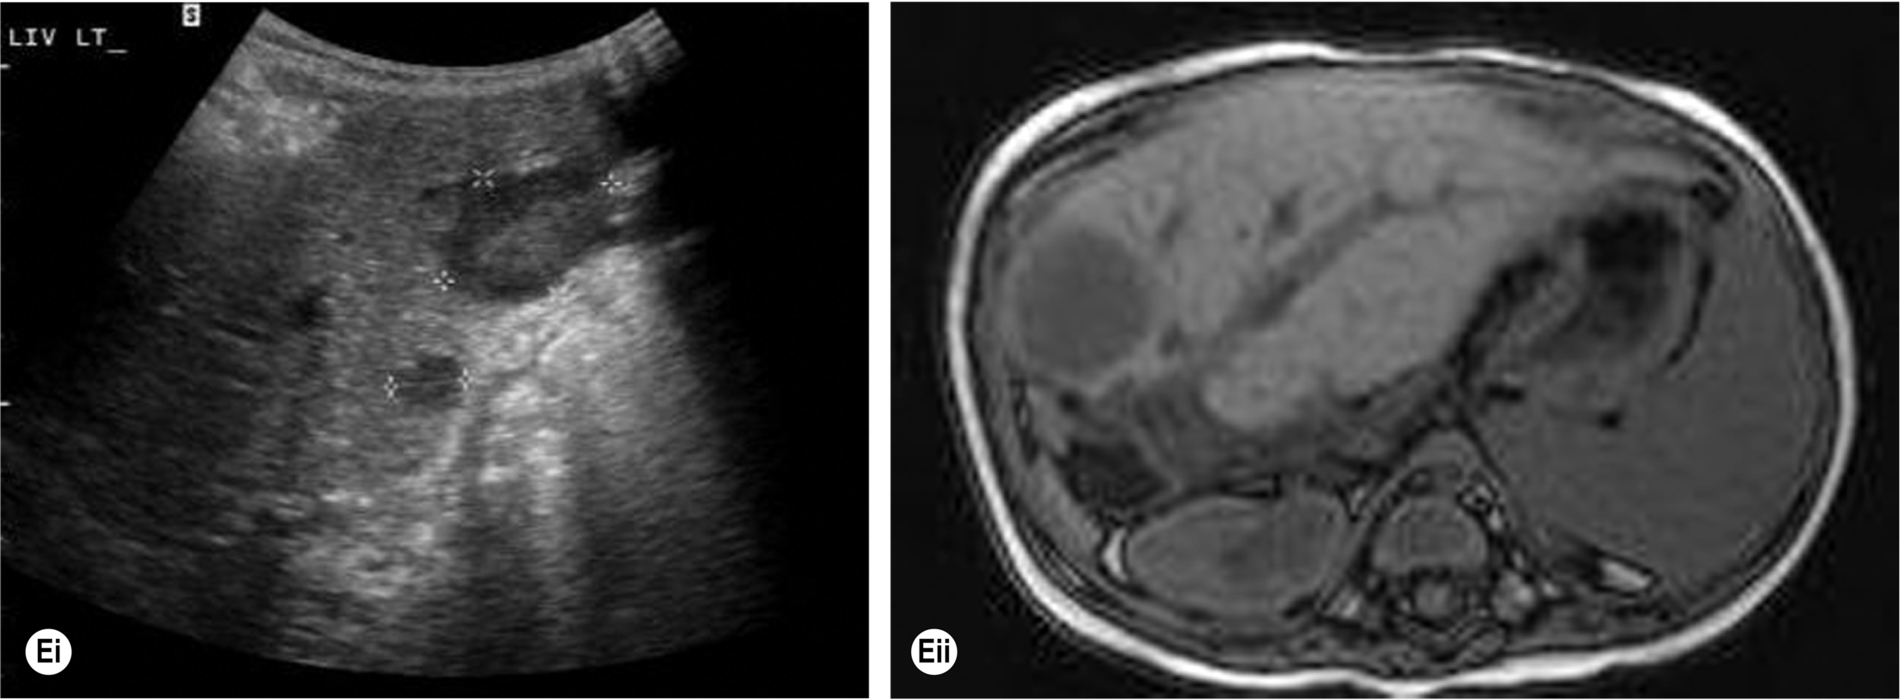

The ultrasound appearances are similar to liver abscesses; they may be single or multiple, hyperechoic, and homogeneous in the early stages, progressing to complex, fluid-filled structures with increased through transmission (Fig. 5.5A–B).

Splenic abscesses are frequently hypoechoic, and it may not be possible to differentiate abscess from lymphoma or metastases on ultrasound appearances alone. This applies both in cases of large solitary abscesses and in multifocal microabscesses. They may also contain gas, posing difficulties for diagnosis as the area may be mistaken for overlying bowel.

Ultrasound findings include multiple hyperechoic lesions throughout the splenic tissue, some of which may display acoustic shadowing (Fig. 5.5C) and is sometimes referred to as “spotty spleen.”

Increased red blood cell destruction, or hemolysis, occurs under two circumstances: when there is an abnormality of the red cells – as in sickle cell anemia, thalassemia, or hereditary spherocytosis – or when a destructive process is at work, such as infection or autoimmune conditions. Fragile red cells are destroyed by the spleen, which becomes enlarged (Fig. 5.6A).

Sickle cell anemia is most prevalent in the black American and African populations. Progression of the disease leads to repeated infarcts in various organs, including the spleen, which may eventually become shrunken and fibrosed. Patients have (non-obstructive) jaundice because the increased destruction of red blood cells releases excessive amounts of bilirubin into the blood.

Due to the variation in appearances, the presence of a hemangioma can give a conundrum, especially when found incidentally. The patient’s clinical history must be taken into consideration; differential diagnoses would include metastases, hematopoiesis, and lymphoma, and in these cases, CEUS, MRI, and CT may be required to aid diagnosis. In cases with a low clinical suspicion of malignancy, such lesions may be followed up with ultrasound and tend to remain stable in size (Fig. 5.6B).

Initially, the area of infarction is hypoechoic and usually wedge-shaped, solitary, and extending to the periphery of the spleen (Fig. 5.7). In the acute phase of infarction, B-mode ultrasound is not often useful, only identifying 50% of infarctions resulting in a high false-negative rate. The lesion may decrease in time and gradually fibrose, becoming hyperechoic. If the infarction is large, it may demonstrate reduced Doppler perfusion when compared to the normal splenic tissue, and CEUS may be particularly helpful in outlining the area of non-perfusion, allowing a definitive diagnosis and is represented as a triangular or slightly rounded area with the base extending to the splenic capsule. In rare cases of total splenic infarction (Fig. 5.7D), because of occlusion of the proximal main splenic artery, gray-scale sonographic appearances may be normal in the early stages.